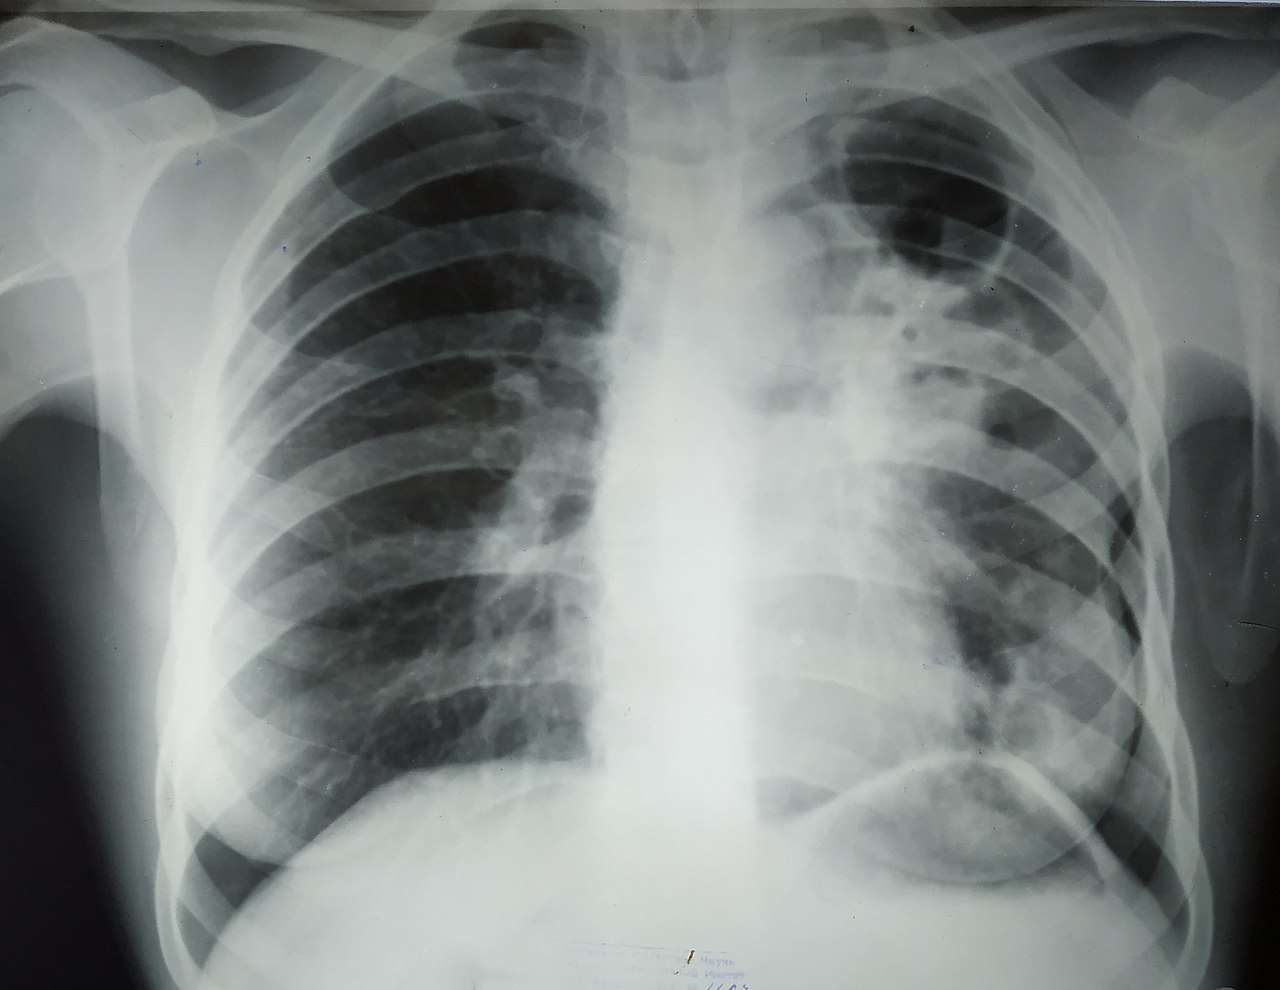

Рентген Больных Легких Фото

Воспаление легких на рентгене - как выглядит, фото . . .

Перед ответом на вопрос о том, как выглядит фото рентген при воспалении легких, важно выделить некоторые особенности, касающиеся самого недуга .